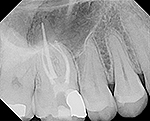

Fig 4. This maxillary first molar was to have endodontic therapy following diagnosis of irreversible pulpitis.

Figure 4

Fig. 5 This maxillary first molar was to have endodontic therapy following diagnosis of irreversible pulpitis.

Figure 5